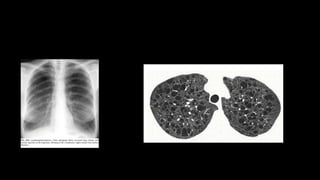

Radiography

• CXR: subtle

increase in

opacity at lung

base

• In early stages, the only HRCT abnormality may be fine reticulation

• Honey combing 3mm to 2 cm, 3 in a row

• reticular opacities

• traction bronchiectasis

• subpleural and lower lobe predominance

• GGOs are rare